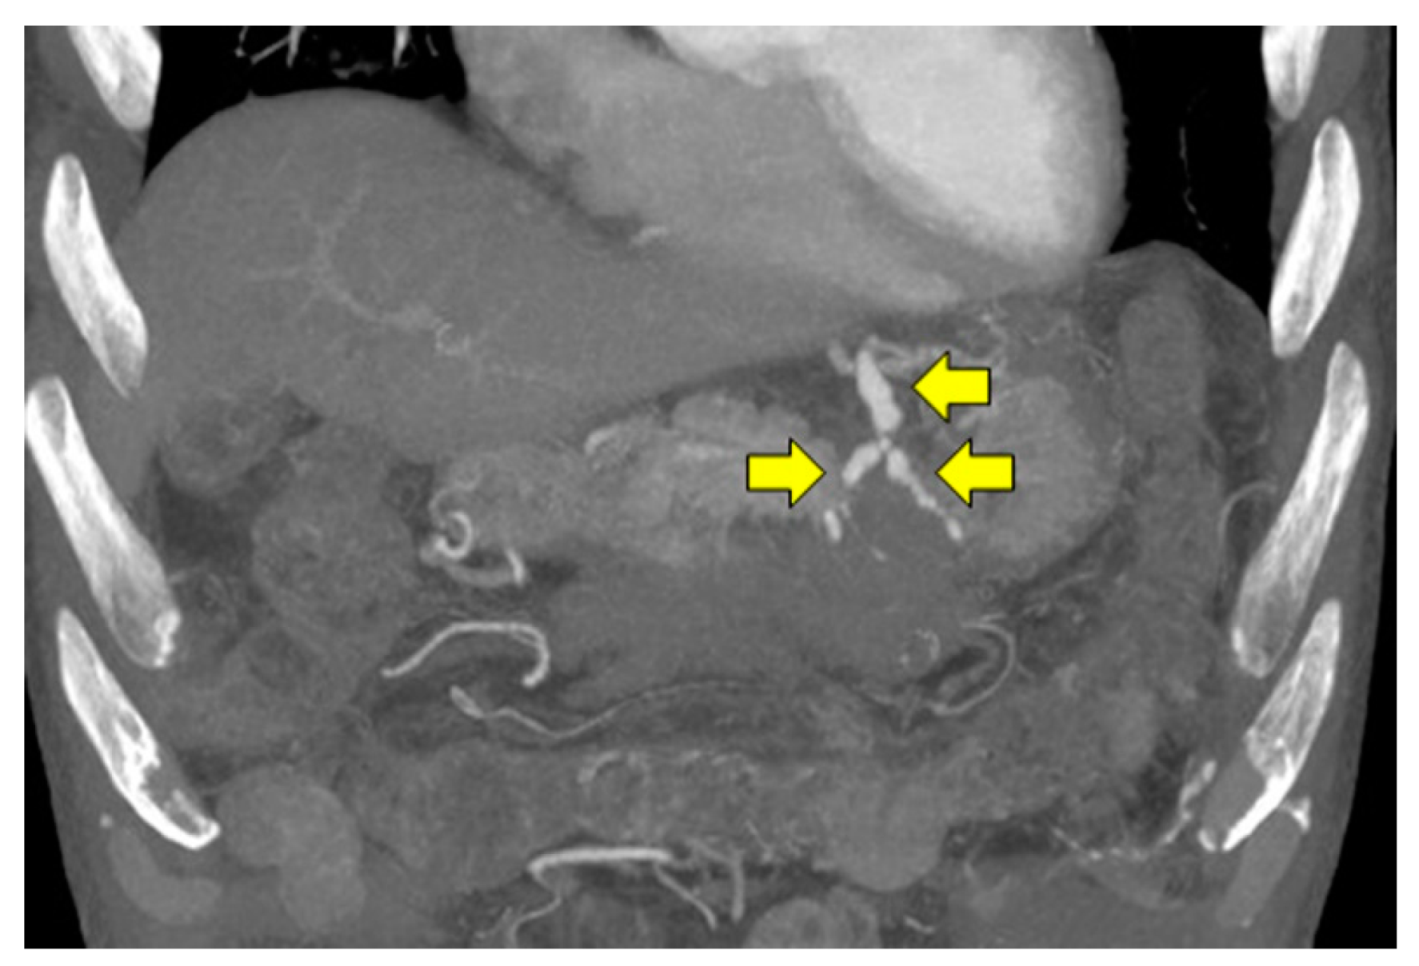

2. Case Presentation